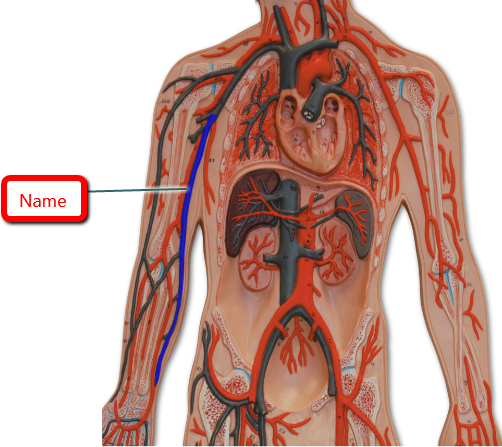

blue

Basilic Vein

Cephalic vein

Great saphenous vein

Median cubital vein

Thoracic aorta

Abdominal Aorta